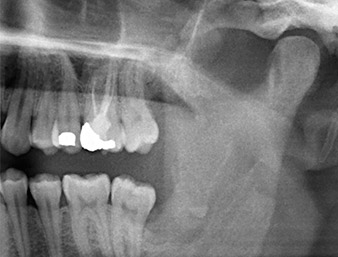

The root remnant in the region of tooth 38 (LL8) was already displaying close proximity to the inferior alveolar nerve on the OPG. The root had fractured during the osteotomy but had not been removed by the primary treatment provider due to intraoperative pain. To ensure as little trauma as possible to the tissue, the new osteotomy was to be carried out using a piezo surgical system. The patient had an unremarkable medical history and was a non-smoker.

OPG 6 months after osteotomy

Fig. 1: OPG 6 months after osteotomy of tooth 38 (LL8): radix relicta lies close to the inferior alveolar nerve.